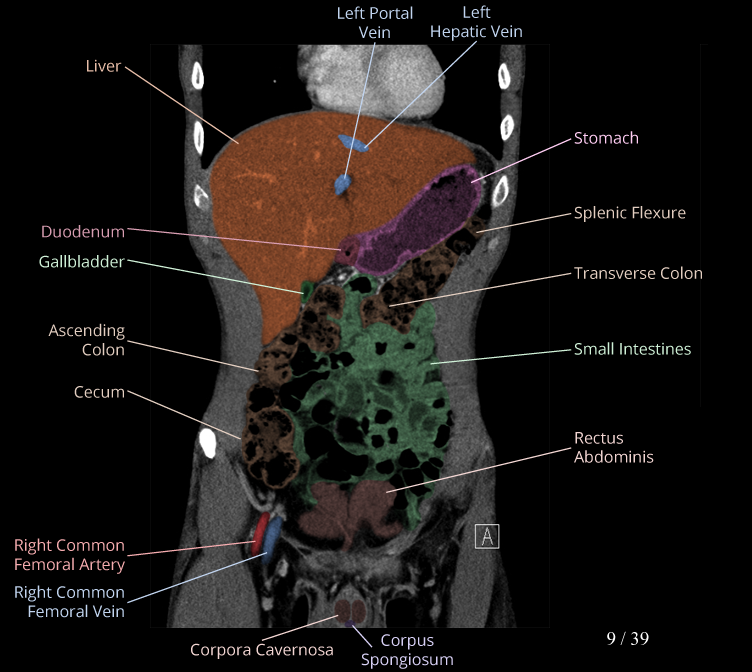

Body

Covers abdominal CT anatomy.